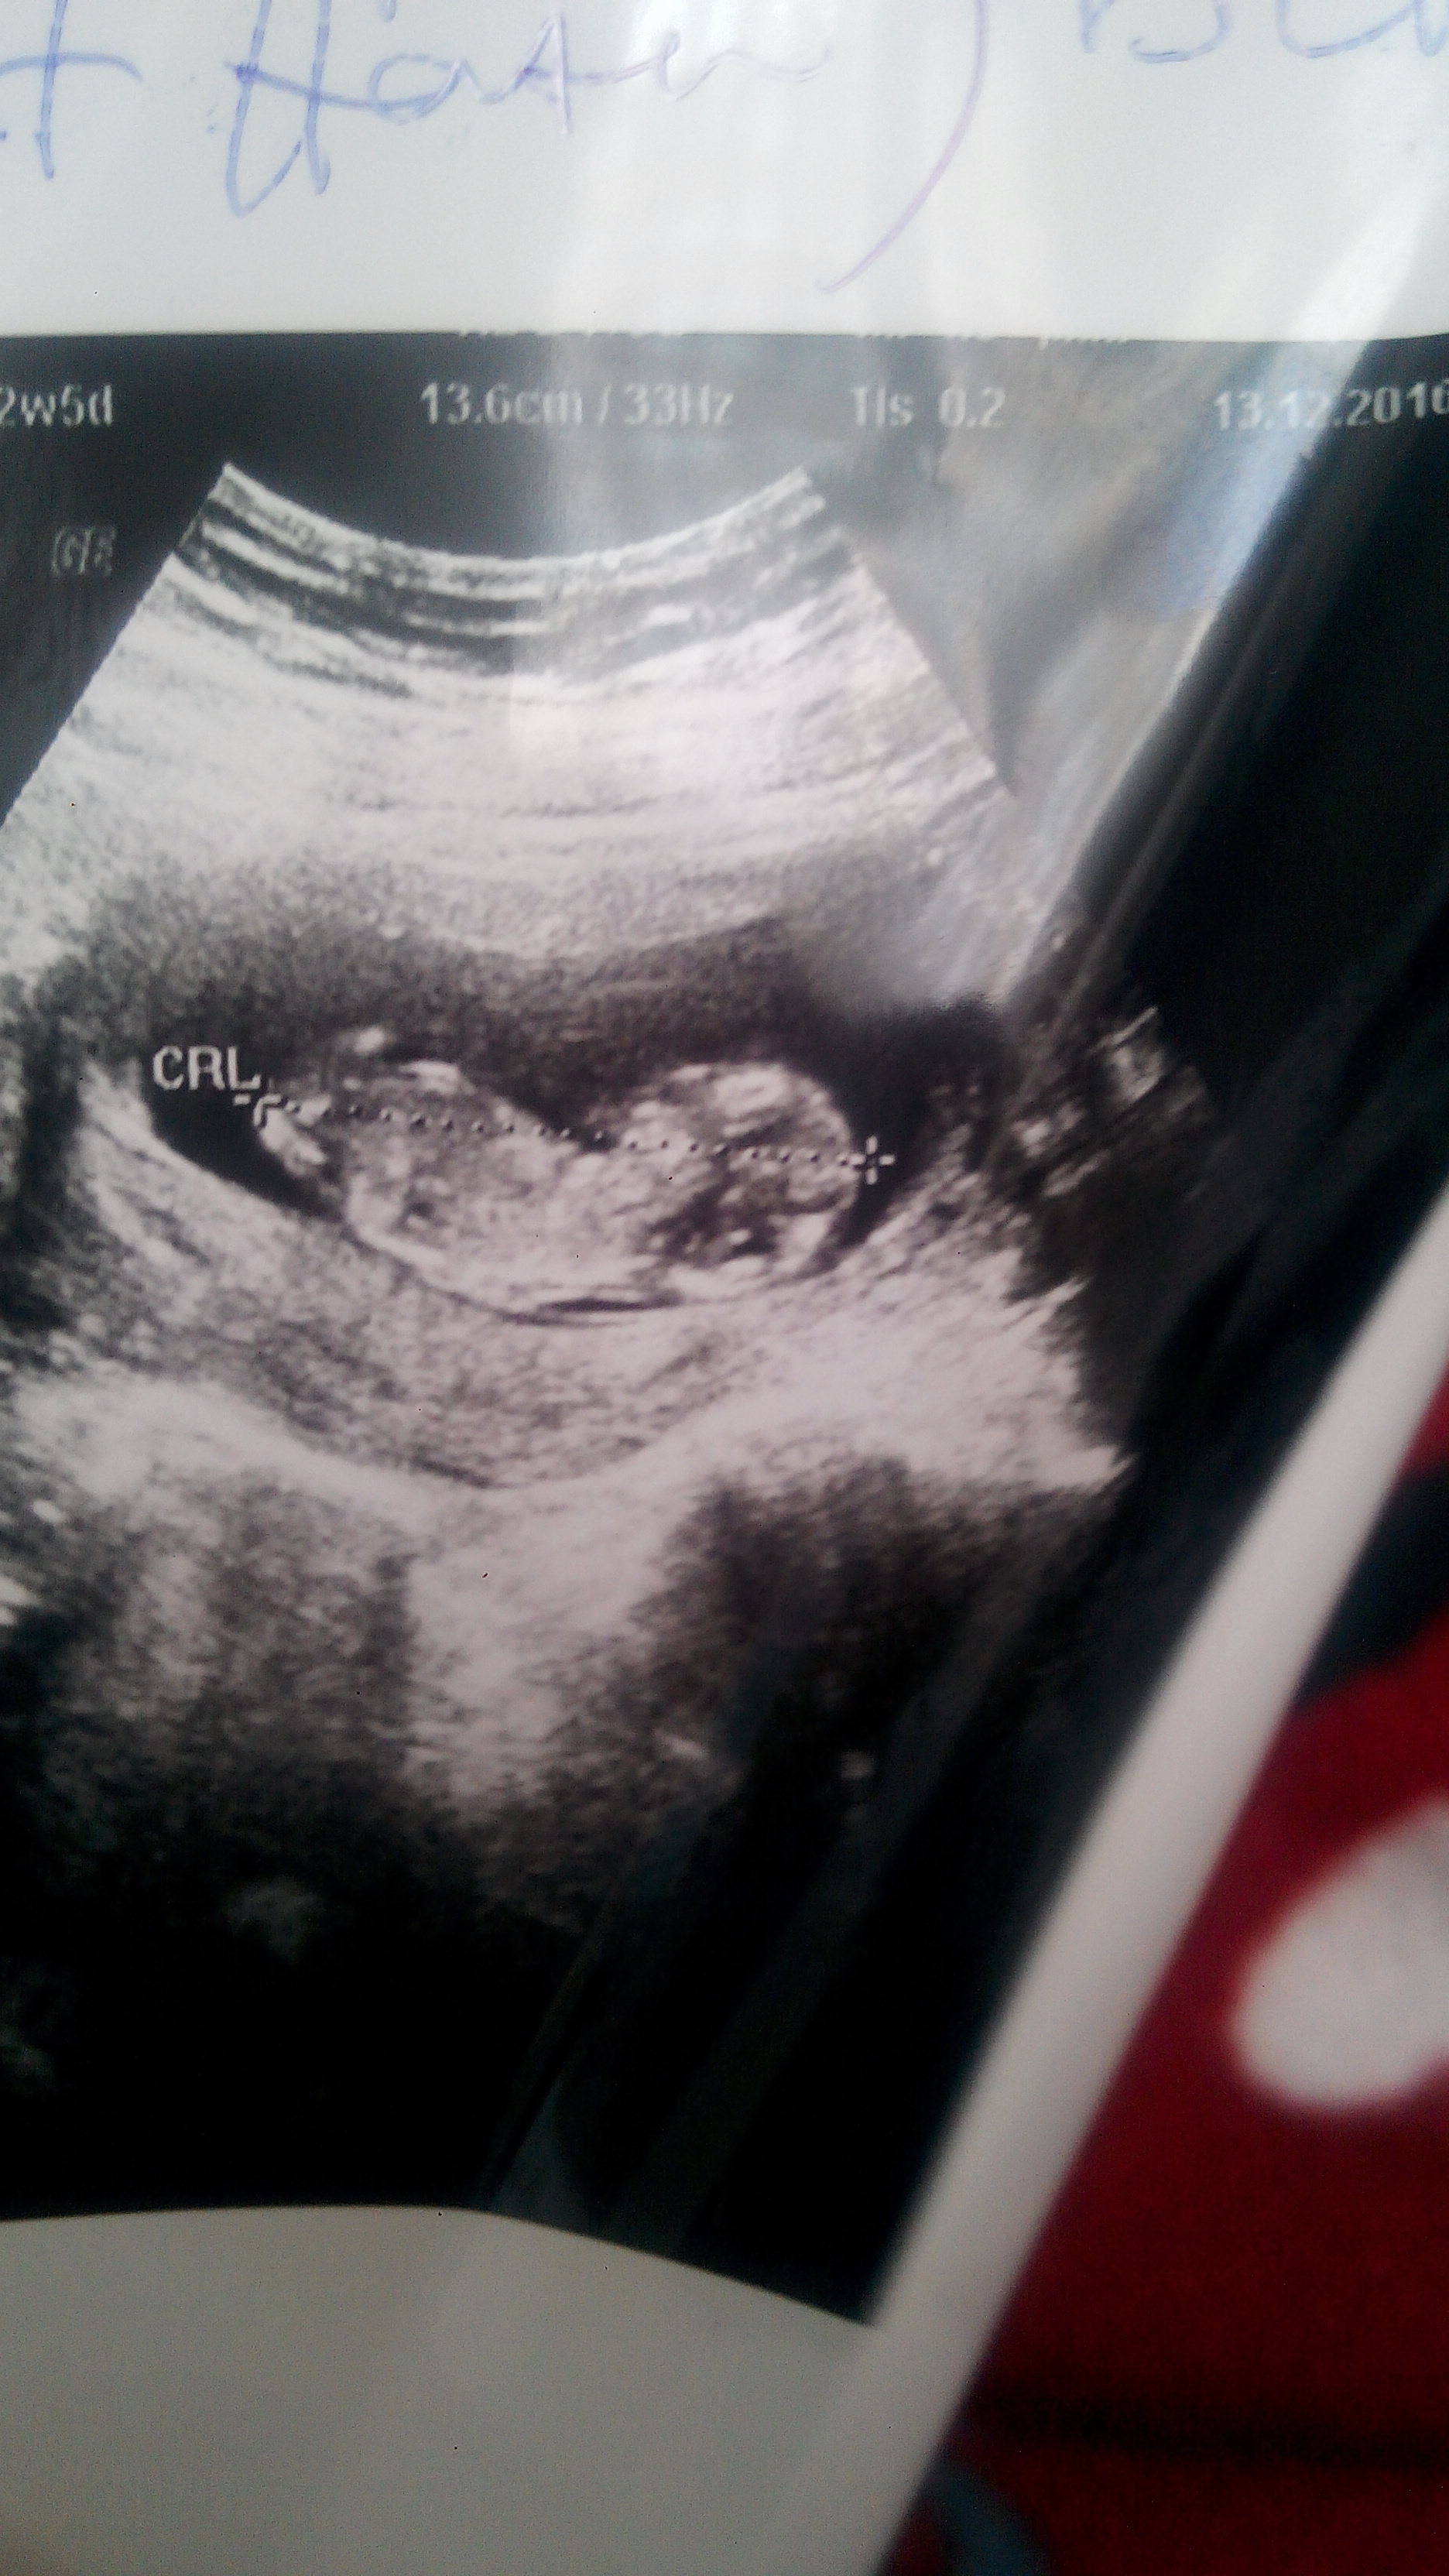

bugunde 15 haftaligiz onuda atacam iki doktora gttim ikiside farkli seyler soylediler

IMG_20170103_161459.jpg

Bu resimde bugunden 15 haftalıgimiz ama hala net bisey yok cinsiyet konusunda iki hafta sonra tekrar gel dedi doktor ama cok sabırsızım saglikli olmasi önceligim tabi ki ama insan merakta etmiyor değil 🙂